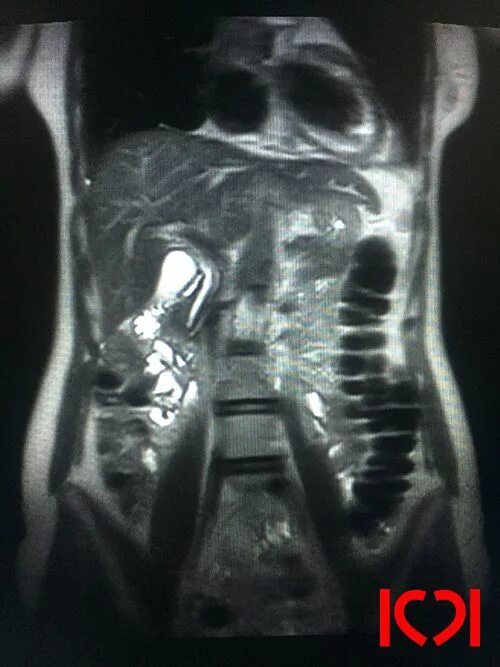

Что входит в мрт забрюшинного пространства